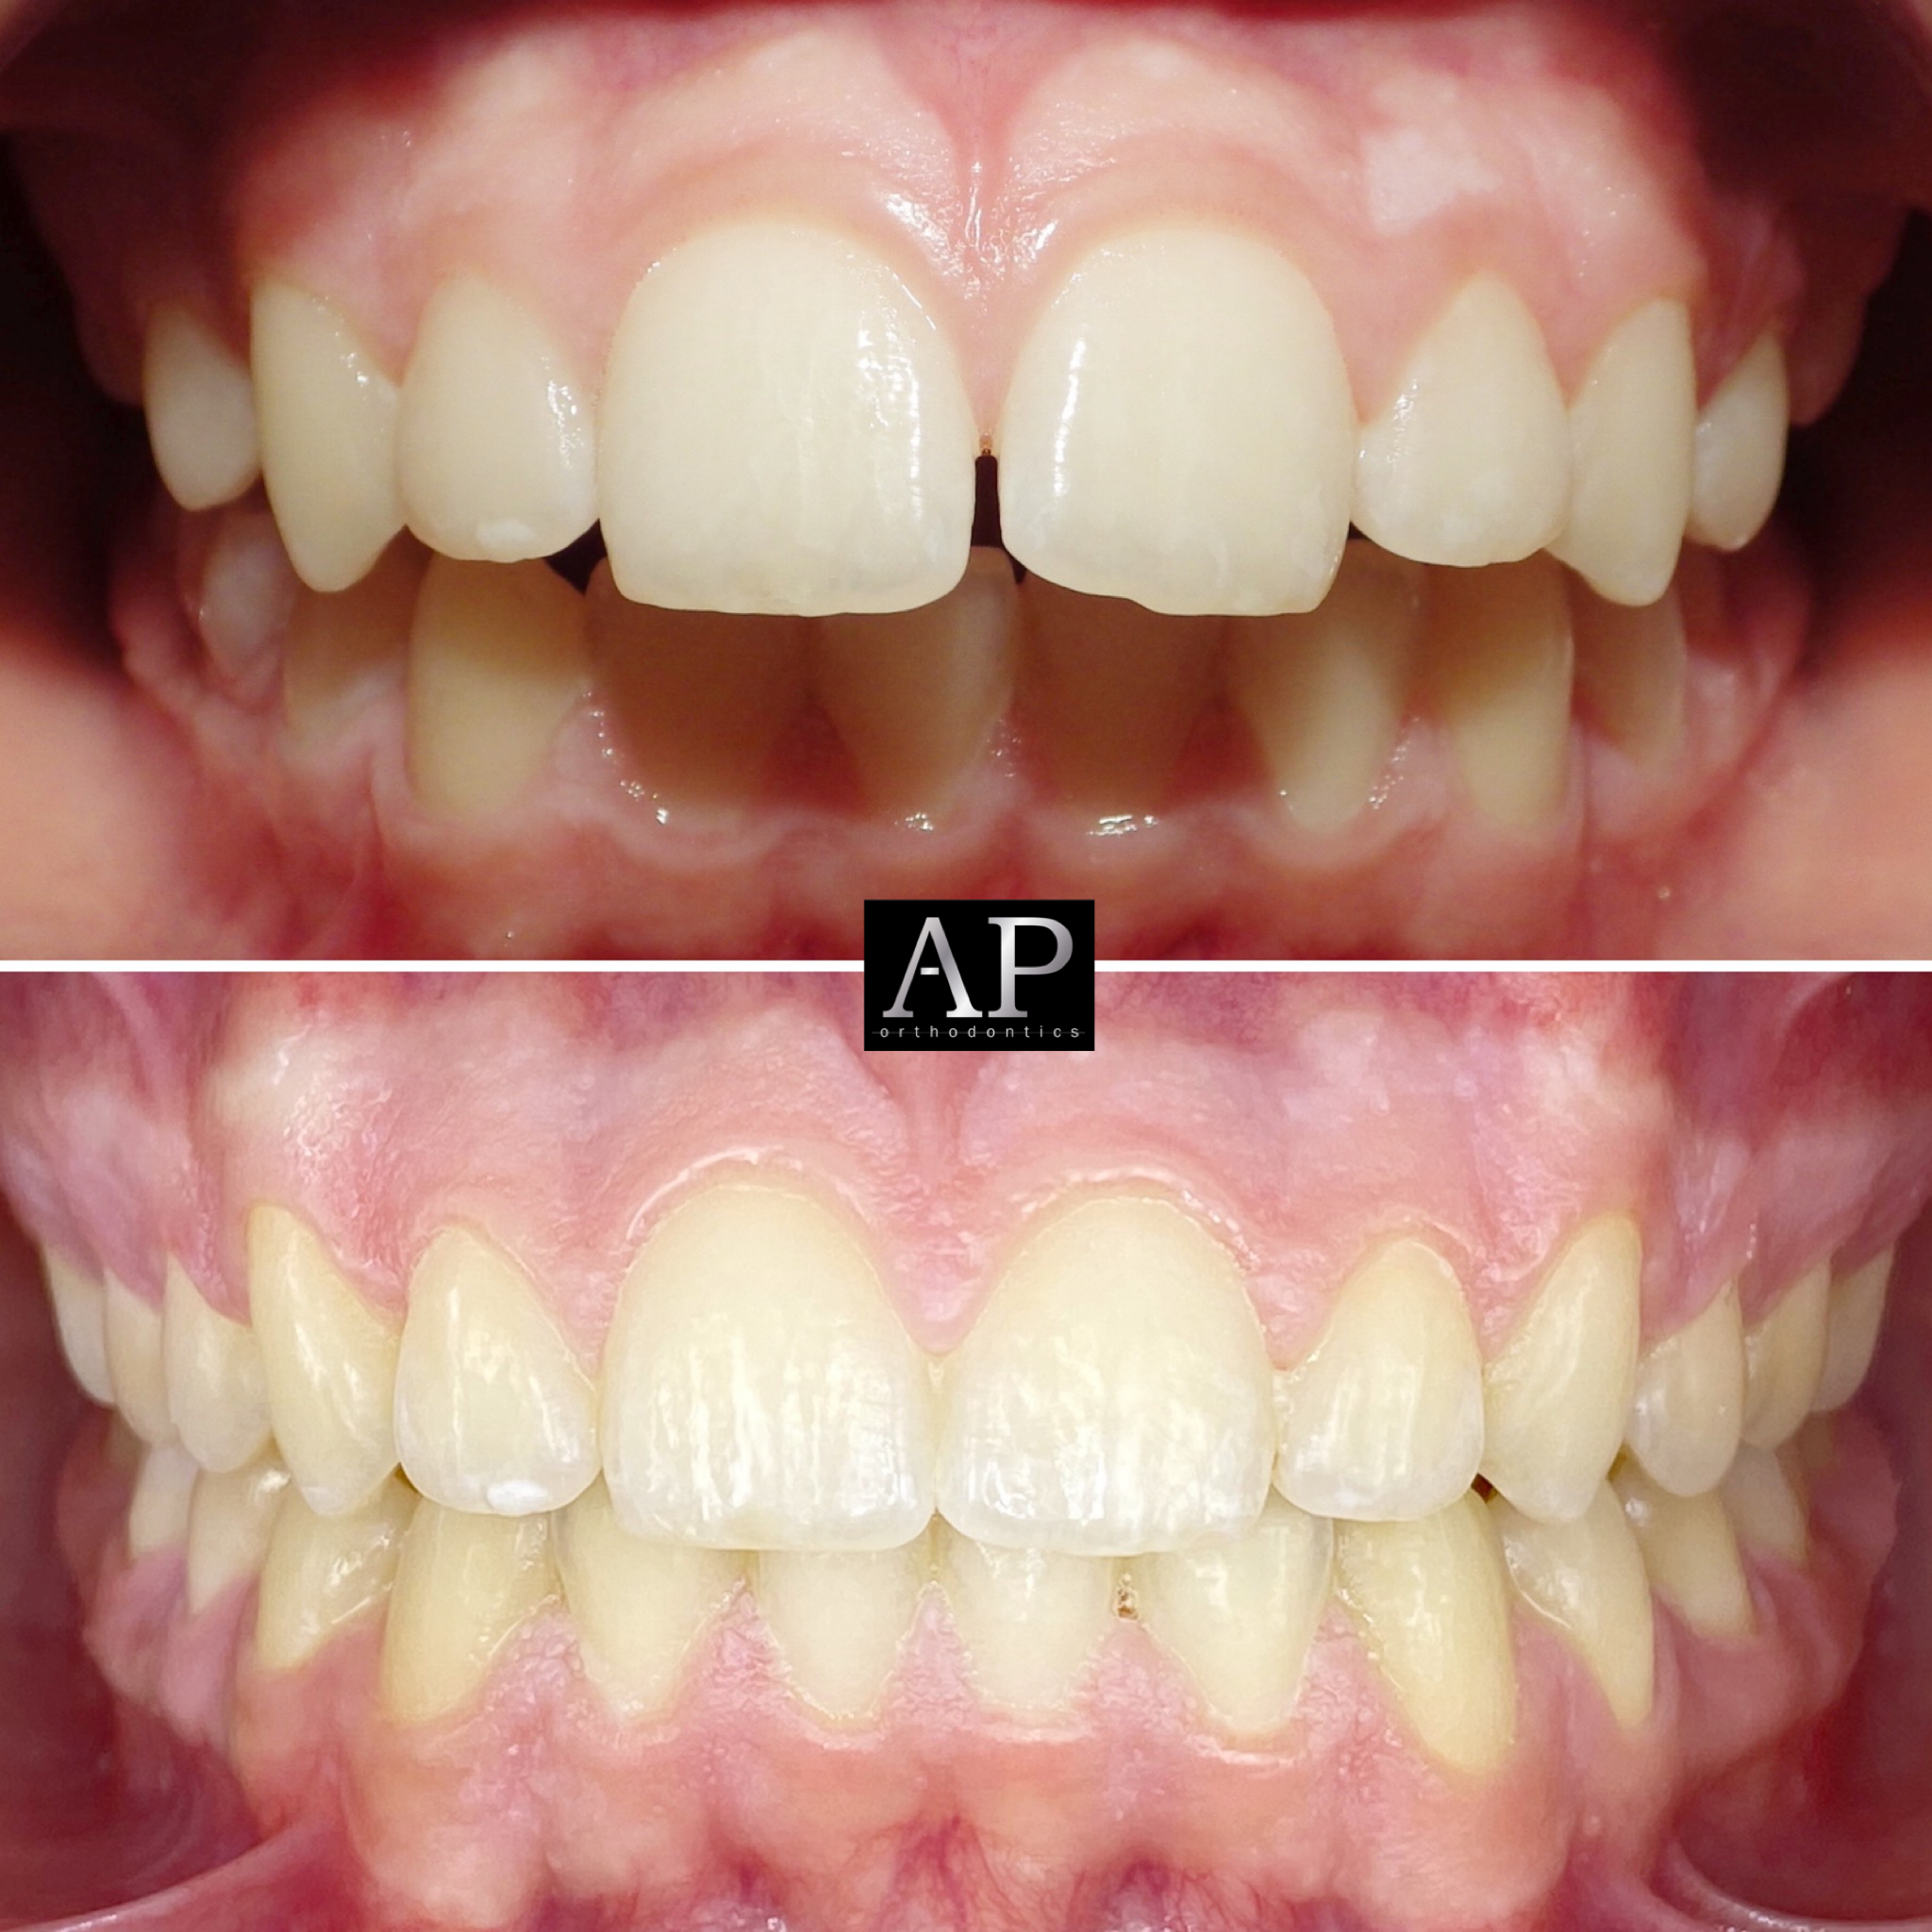

Ορθοδοντικό ιατρείο

Διαφανείς νάρθηκες

Σιδεράκια

Αόρατη ορθοδοντική

Συμβατική ορθοδοντική

Διάφανα σιδεράκια

Σιδεράκια κεραμικά (λευκά)

Ορθοδοντικό ιατρείο

Διαφανείς νάρθηκες

Σιδεράκια

Αόρατη ορθοδοντική

Συμβατική ορθοδοντική

Διάφανα σιδεράκια

Σιδεράκια κεραμικά (λευκά)